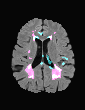

In recent years, data-driven machine learning (ML) methods have revolutionized the computer vision community by providing novel efficient solutions to many unsolved (medical) image analysis problems. However, due to the increasing privacy concerns and data fragmentation on many different sites, existing medical data are not fully utilized, thus limiting the potential of ML. Federated learning (FL) enables multiple parties to collaboratively train a ML model without exchanging local data. However, data heterogeneity (non-IID) among the distributed clients is yet a challenge. To this end, we propose a novel federated method, denoted Federated Disentanglement (FedDis), to disentangle the parameter space into shape and appearance, and only share the shape parameter with the clients. FedDis is based on the assumption that the anatomical structure in brain MRI images is similar across multiple institutions, and sharing the shape knowledge would be beneficial in anomaly detection. In this paper, we leverage healthy brain scans of 623 subjects from multiple sites with real data (OASIS, ADNI) in a privacy-preserving fashion to learn a model of normal anatomy, that allows to segment abnormal structures. We demonstrate a superior performance of FedDis on real pathological databases containing 109 subjects; two publicly available MS Lesions (MSLUB, MSISBI), and an in-house database with MS and Glioblastoma (MSI and GBI). FedDis achieved an average dice performance of 0.38, outperforming the state-of-the-art (SOTA) auto-encoder by 42% and the SOTA federated method by 11%. Further, we illustrate that FedDis learns a shape embedding that is orthogonal to the appearance and consistent under different intensity augmentations.